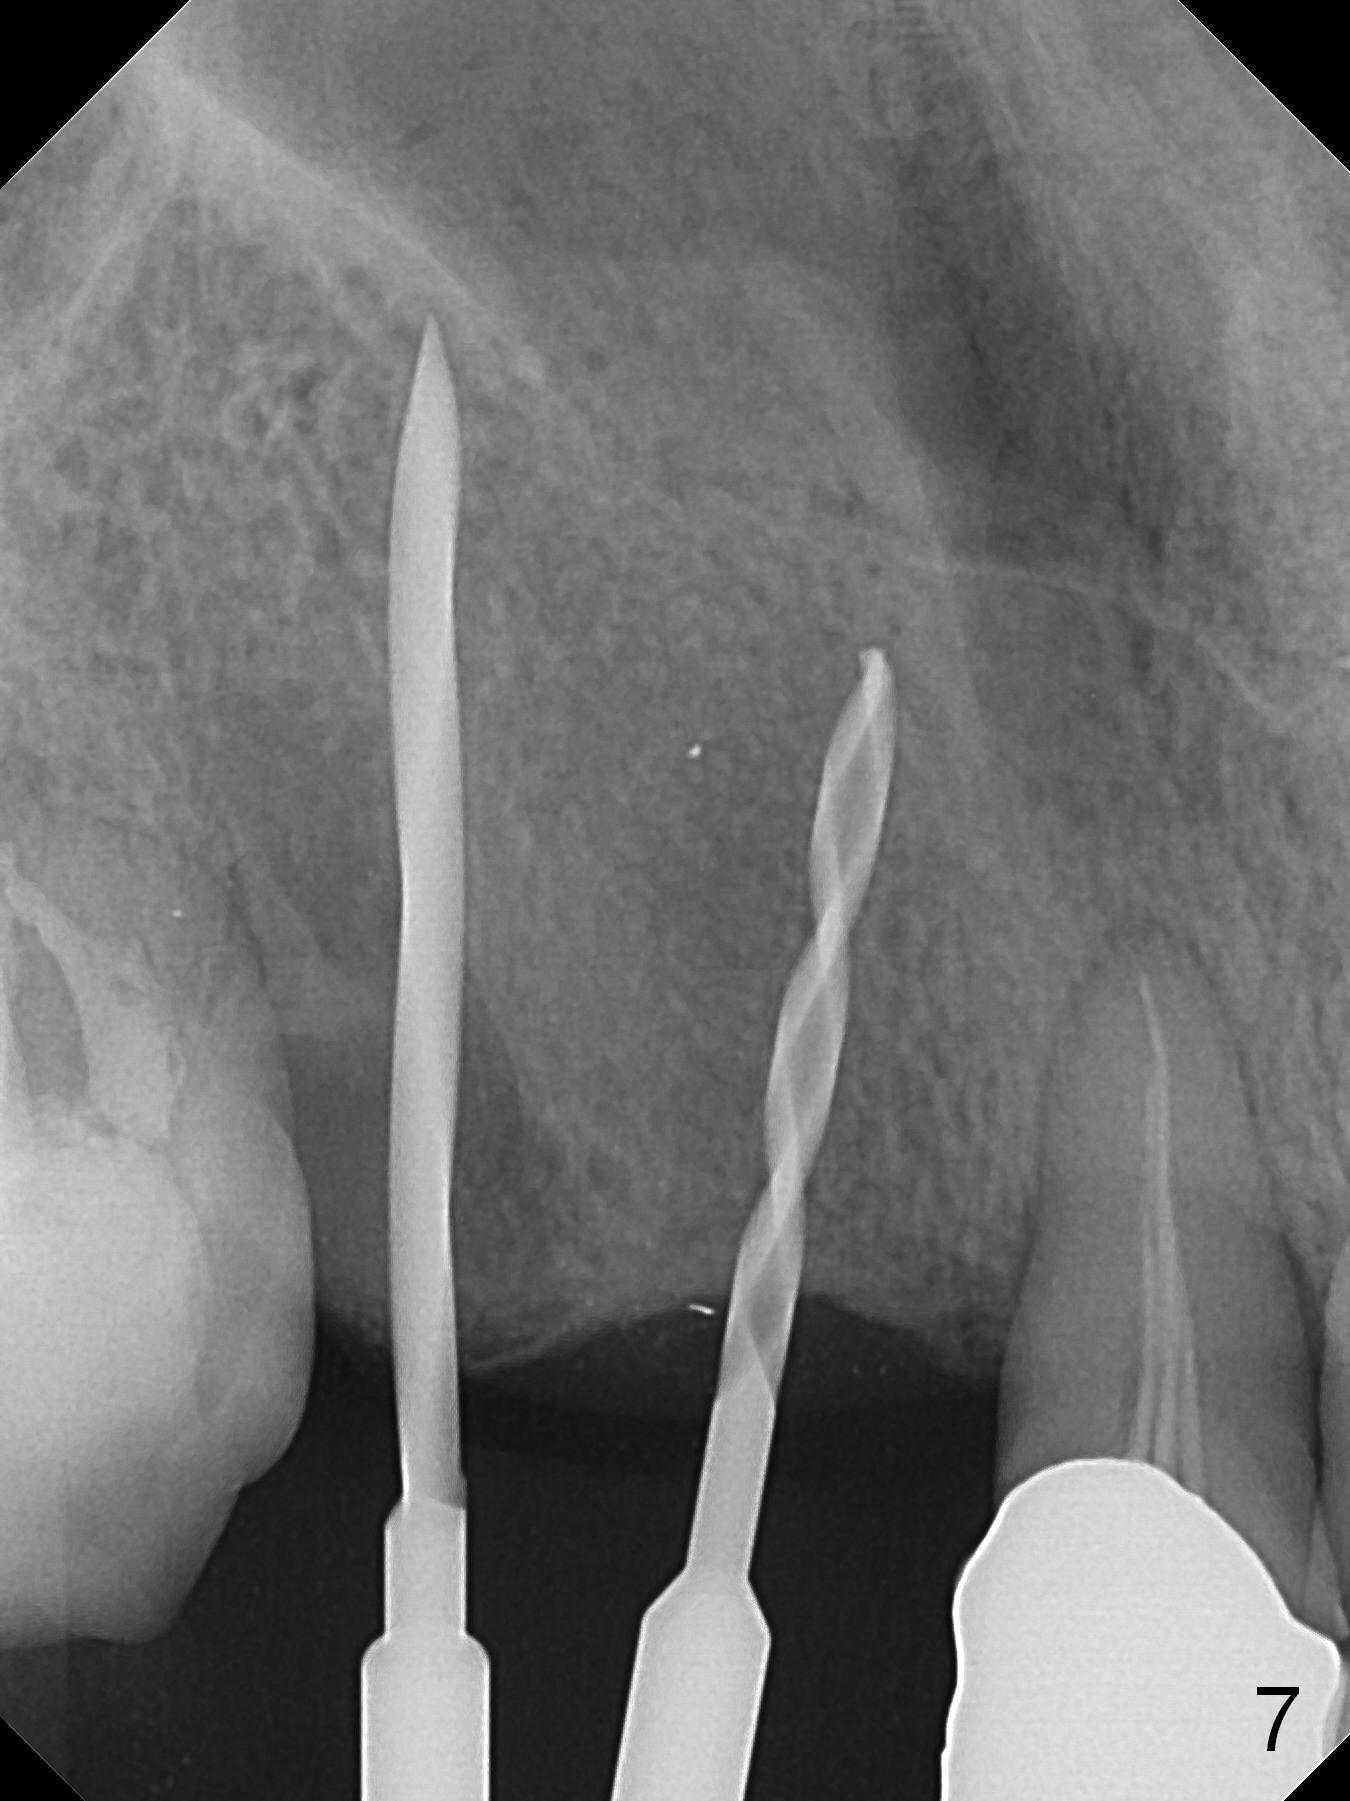

When the bridge is sectioned between #7 and 8, the tooth #6 is found non-salvageable (Fig.1).  Incision shows the atrophic buccal plate at #7 (Fig.2 arrowheads); to prevent the same feature from happening at #6 with thin buccal plate, the most buccal portion of the root is preserved (socket shield (Fig.2-4: *)).  The initial osteotomy is established in the palatal slope at #6 (Fig.5 circle) with 1.5 mm drill (Fig.6,7).  A portion of the root is visible in Fig.6 (arrowheads).  After sequential osteotomy with 2 mm, 3 mm (Fig.8) and 3.2 mm drills, a 4x15 mm implant is placed (Fig.10).  To accommodate the cross bite, the coronal portion of the implant (Fig.9 white circle) is positioned close to the socket shield.  It appears that the shield prevents the implant from encroaching the buccal plate.

Since the ridge at #7 is ~ 4 mm, a 2.5x14 mm 1-piece implant is placed (Fig.8) after 1.2 mm (Fig.7), and 1.5 mm drills at 12 mm and 2 mm drill at 8 mm.  Later the implant is placed deeper (Fig.10).  There is no bone loss 7 or 12 months postop, respectively (Fig.11,12).  After Diode gingivectomy, there is papillary formation (Fig.13).  No provisional is provided after impression (with the abutment torqued at #6) for oral hygiene.  With access holes at #6 and 7, crowns are bonded with minimal residual cement (Fig.14 <, which is removed later).  There is no hard (Fig.15,16) or soft (Fig.17 *) atrophy 26 months postop, i.e., 13 months post cementation, due to the presence of socket shield (Fig.15 <, as compared to Fig.1).  In fact the tooth #8 has mobility and fremitus (short root/poor crown/root ratio, Fig.16); occlusal adjustment is done 13 months post cementation.  The crown is dislodged 2 years 1 month post cementation; a prefabricated post is being tried in (Fig.18).  There is no atrophy, bone loss or infection at #6 (with socket sheath (*)) or 7 two years 5 months post cementation (Fig.20-27).